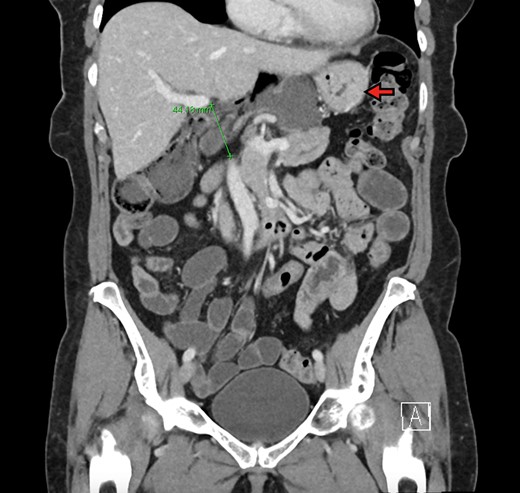

The patient is a 70-year-old woman who presented to the emergency department with acute-onset abdominal pain throughout her epigastrium for approximately 2 hours. The pain was constant and severe, extending across the bilateral upper quadrants. She had experienced pain like this once before within the past year which spontaneously resolved within 4 hours. The patient’s last oral intake was an hour before onset of the pain, and she denied any fevers, chills, nausea or vomiting. She was an otherwise healthy woman who took no medications and had no abdominal surgical history. On admission, vital signs were normal, with a heart rate in the 70’s. Although initially reported as tender by emergency department staff, after pain medication and intravenous fluids, examination by the surgical team revealed resolution of pain and a soft, non-tender abdomen. Lactic acid on presentation was 5.0 mmol/l, and her white blood cell count was 9600 µl−1, with the remainder of her laboratory values within normal limits. She underwent a computed tomography scan which demonstrated herniation of her cecum through the FoW, causing compression of the inferior vena cava (IVC) and portal vein (Figures 1–3).

The cecum is absent from the right lower quadrant and is located between the liver and stomach (red arrow) visualized as an air-fluid level (green arrow). Compression of the portal vein by herniated contents is demonstrated (blue arrow).